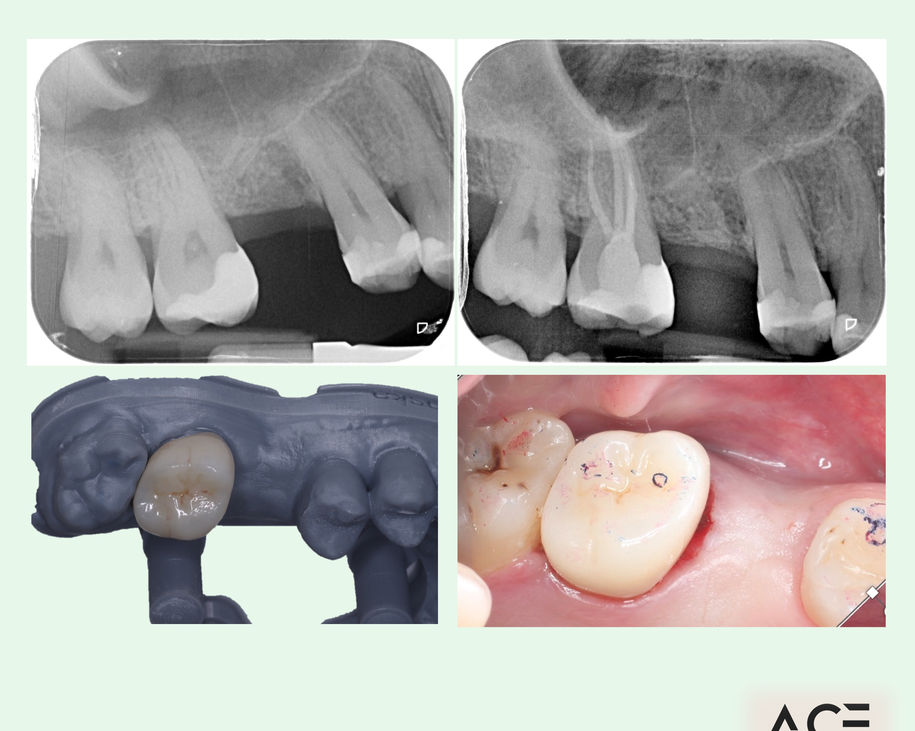

Alumni Outcomes showcasing below snippets of cases submitted as part diploma submissions

Dentists transitioning from routine dentistry into advanced restorative cases

Improved treatment planning confidence

Predictable clinical outcomes through structured protocols